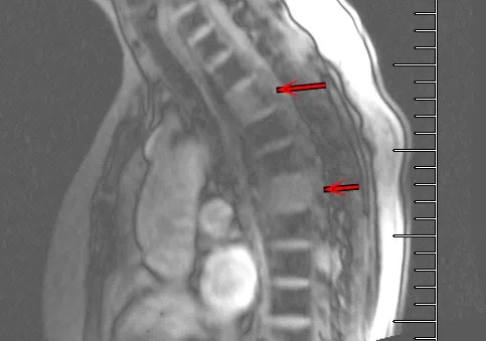

胸椎MR

那么这是原发性的还是转移性的?如果是原发的,就要搞清楚这是哪种类型的骨肿瘤。如果是骨转移,又是哪里转移过来的?我们知道,除了头发和指甲不能发生癌变,其他位置都有可能出现肿瘤,而这些地方的肿瘤都有发生骨转移的几率。还得继续做检查明确。接着医生让做了胸腹盆的CT,CT提示了更多的转移,在肺、纵隔、右侧腋窝都出现了转移灶,依然没办法确定原发病灶。那么原发灶在哪里呢?这时管床医生想到了核医学科的PET/CT。